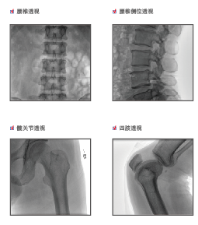

普愛醫(yī)療是專業(yè)從事平板小C生產(chǎn)、研發(fā)、售后為一體的廠家,目前我們應用在國內(nèi)很多醫(yī)院的一款PLX118F平板C形臂,它是一臺集光、機、圖像處理技術(shù)為一體的帶數(shù)字減影血管造影功能(DSA)的可移動式X光機,該設(shè)備占地面積小、圖像清晰、定位精準、輻射劑量小,是疼痛科醫(yī)生的可靠眼睛,對于疼痛介入手術(shù)的精準化治療、滿足患者對慢性疼痛治療需求提供了有利條件。